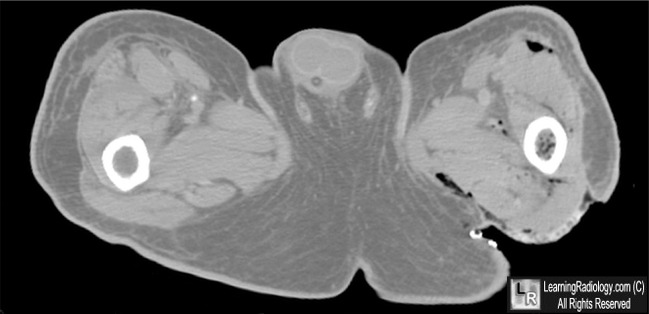

Necrotizing Fasciitis. Axial CT scans taken through the upper thighs show gas in the soft tissue fascial planes

(white circle and white arrows) in a patient with extreme tenderness in this region.